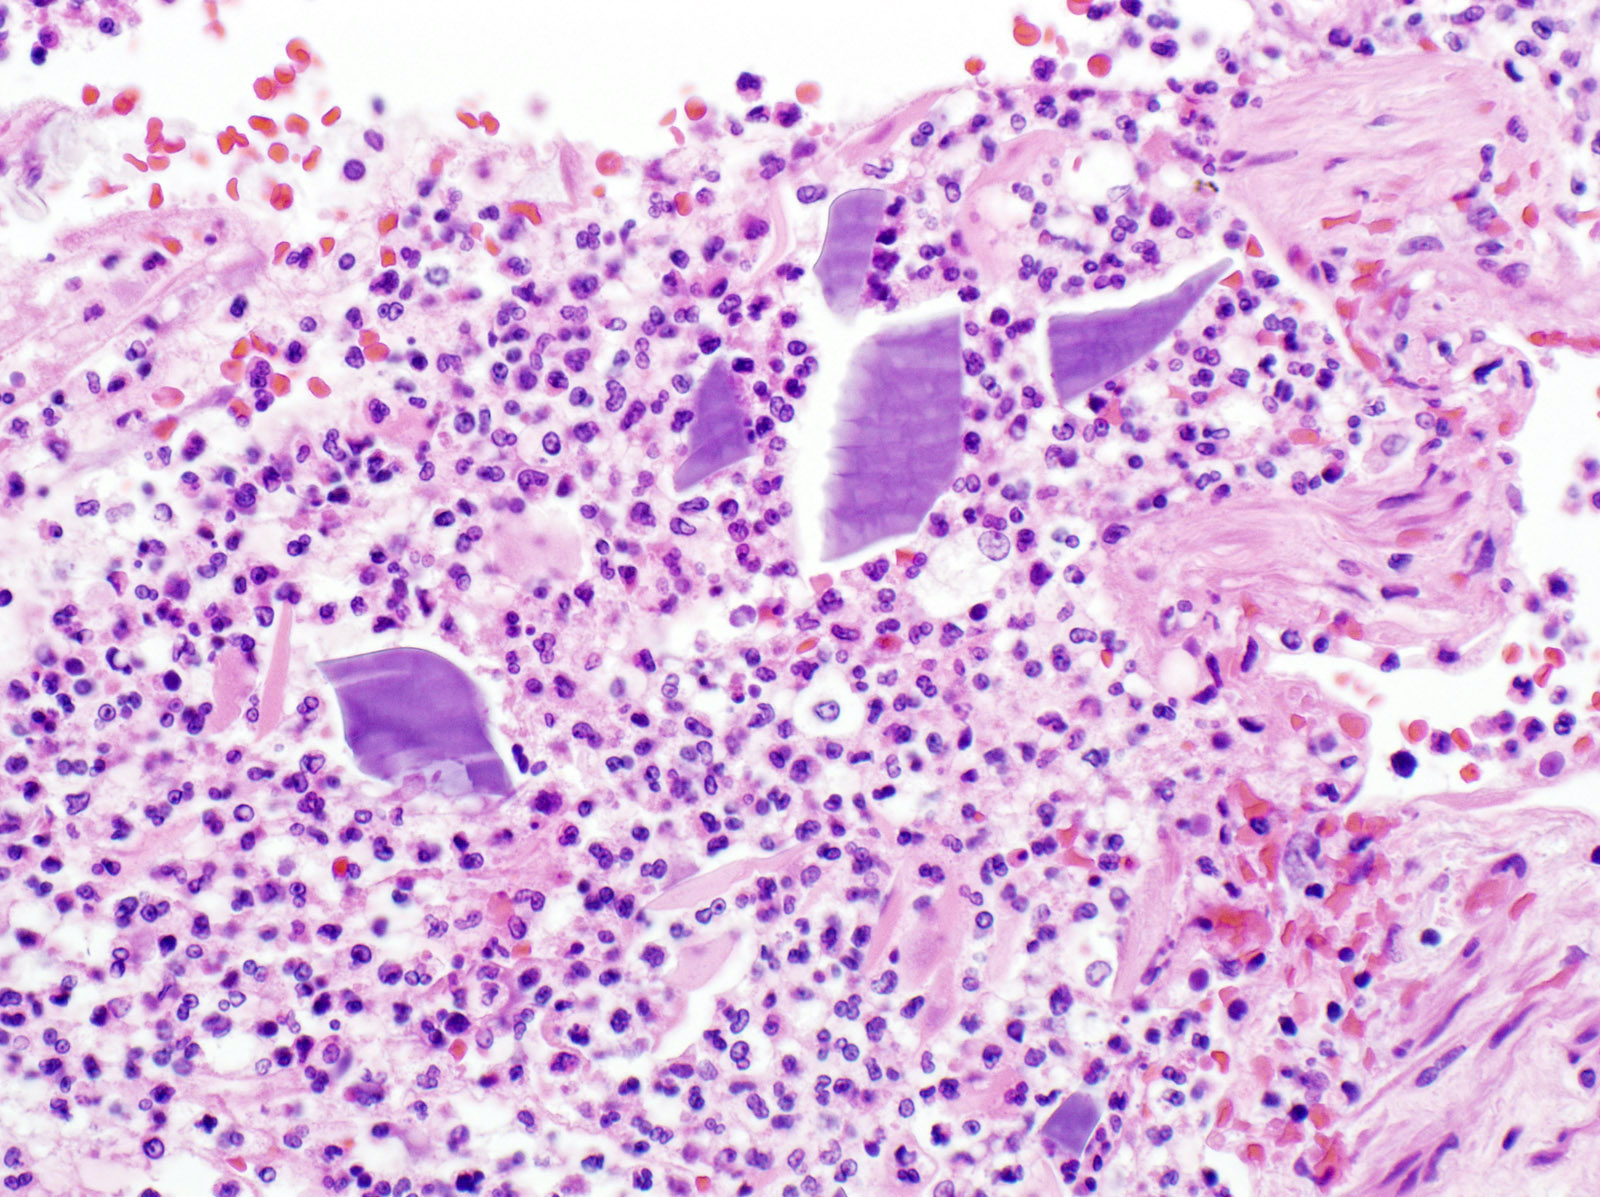

Microscopic (histologic) description

- Aspiration pneumonia:

- Foreign body giant cell reaction, characterized by multinucleated giant cells, granulomatous inflammation

- Often necrotizing, abscess formation is common

- Presence of food particles (e.g., lentils, vegetables, pill fragments)

Microscopic (histologic) images